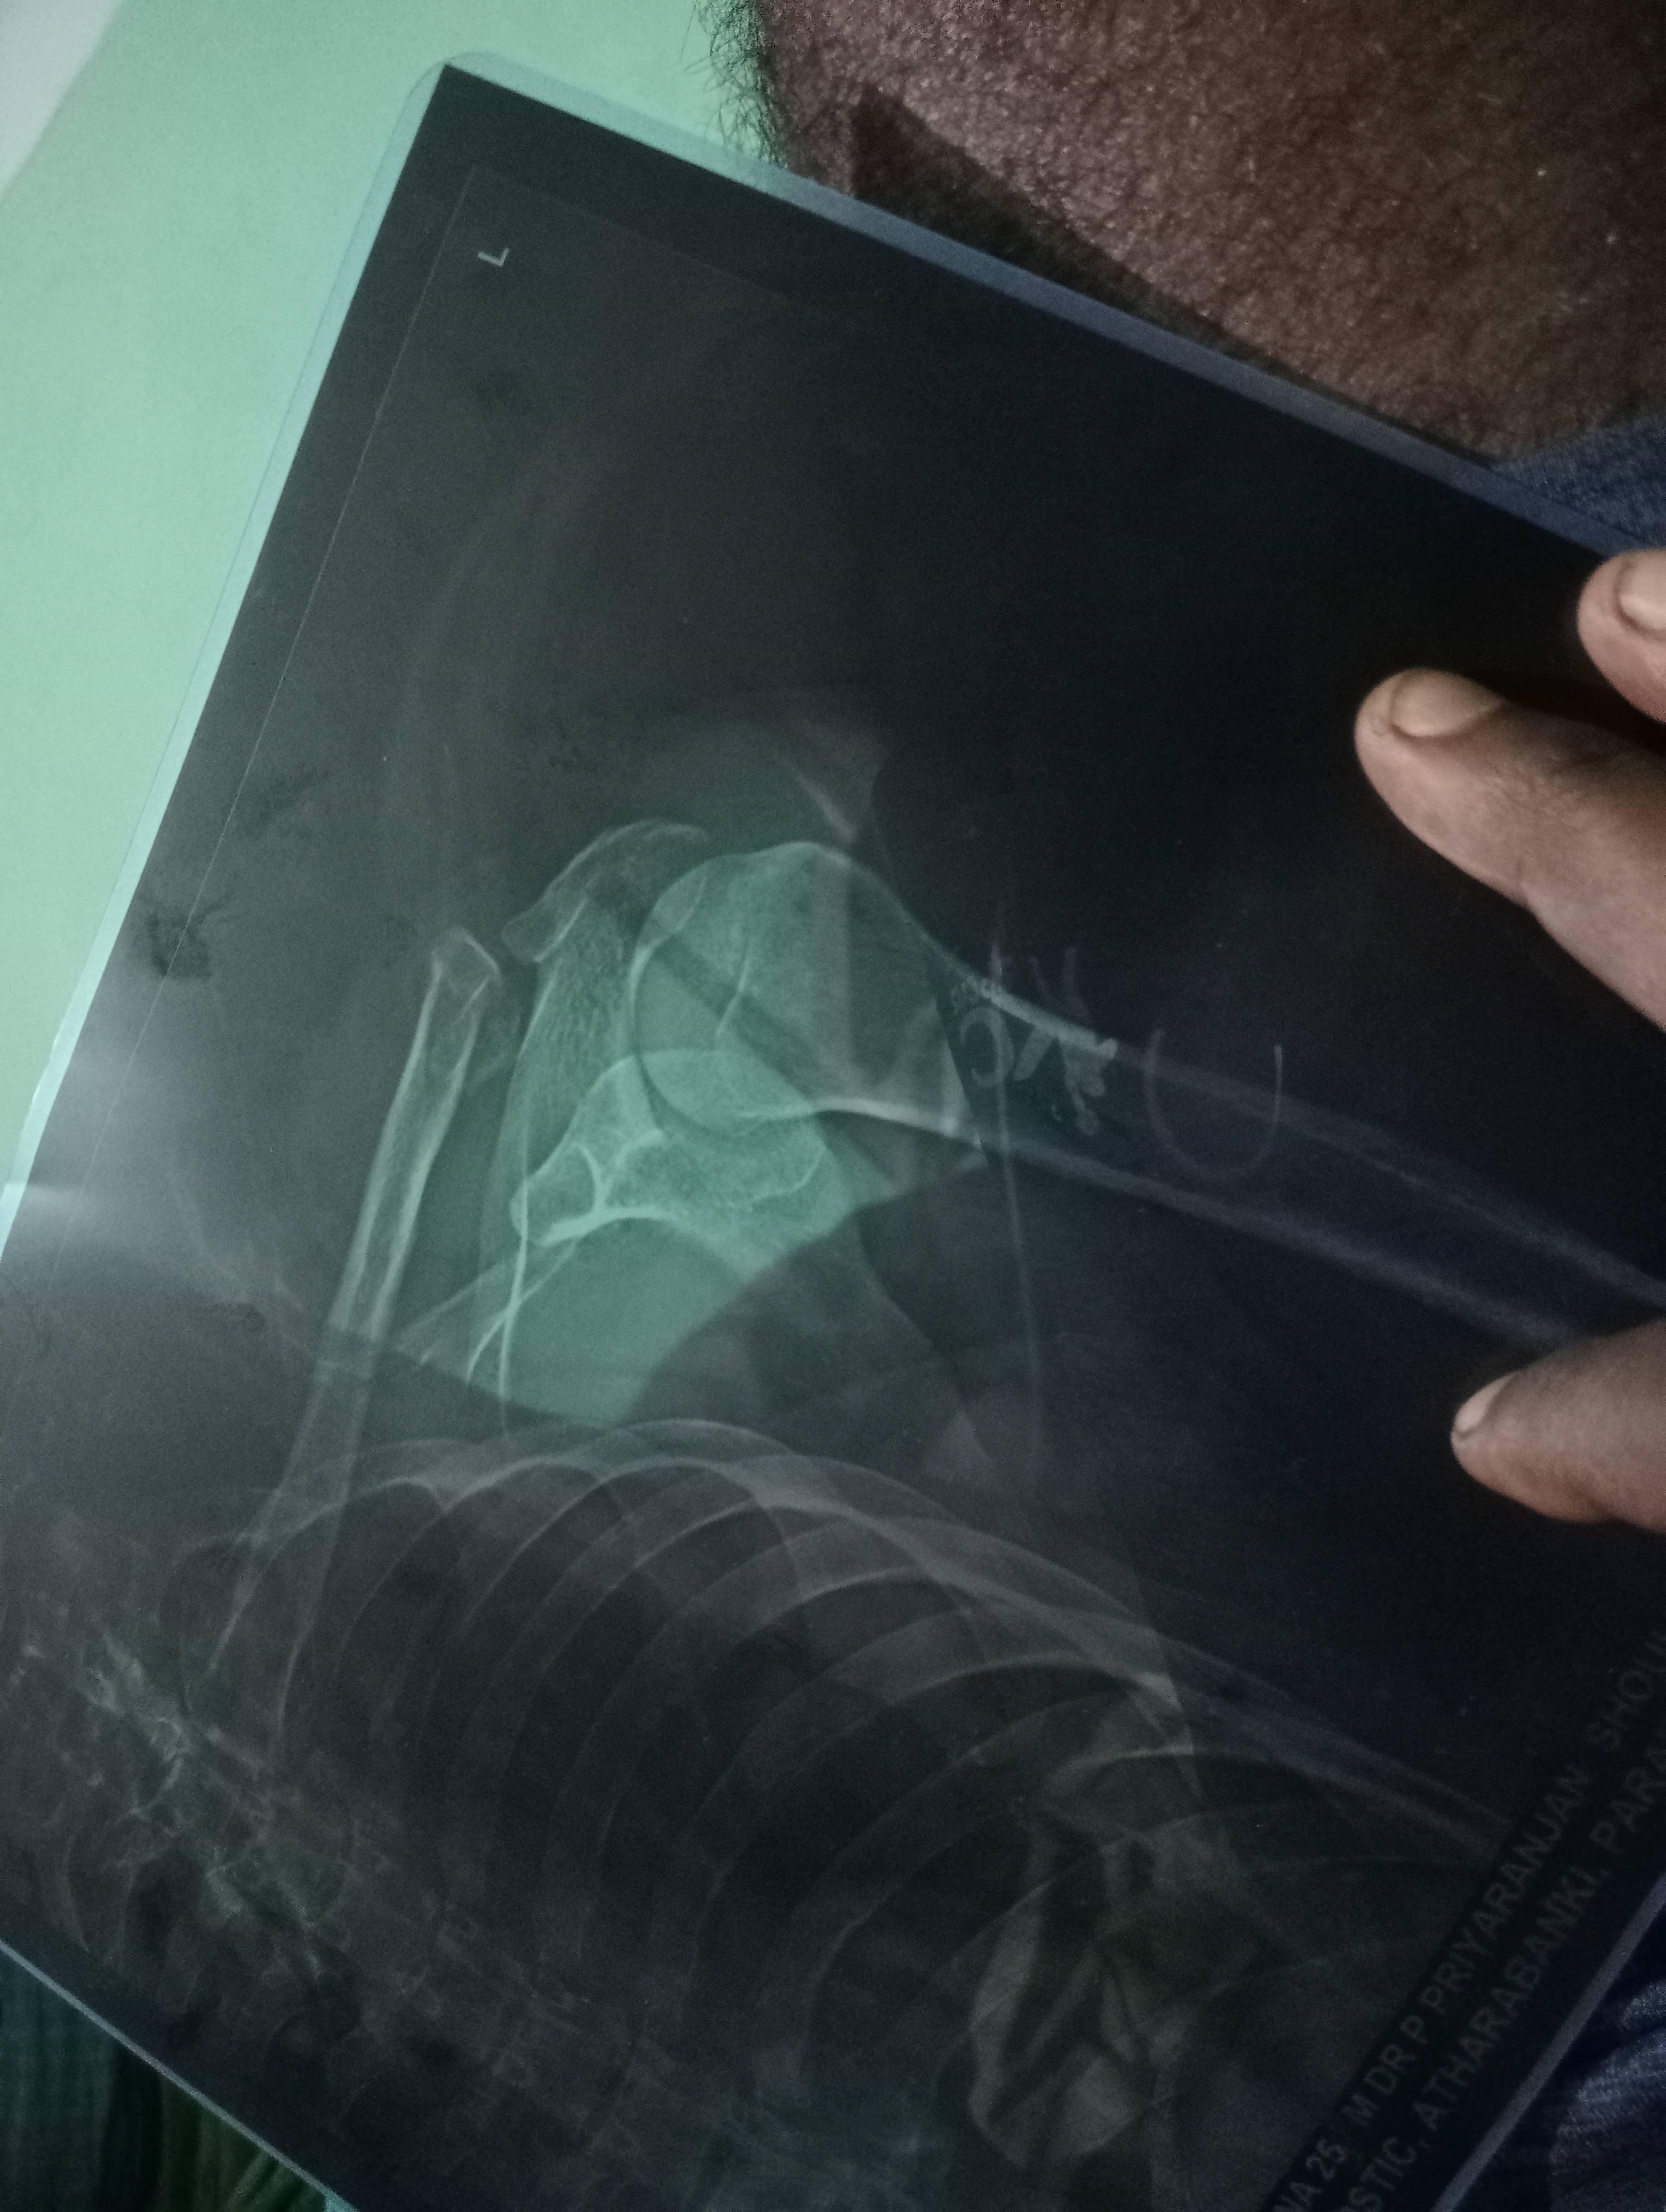

What is opinion about this fracture